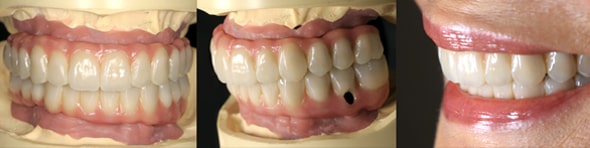

とびきり美しい上部構造

ただ治すのではなく、美しく治す。しかも、とびっきり美しく治すことにこだわっています。そのため、数々の賞を受賞する腕の良い歯科技工士と連携して歯をデザインしています。

3Dスマイルデザイン、ワックスアップ、ラジオグラフィックガイド等によるプランニングに基づいて、患者様それぞれに合わせたオーダーメイドの治療を慎重に進めていきます。